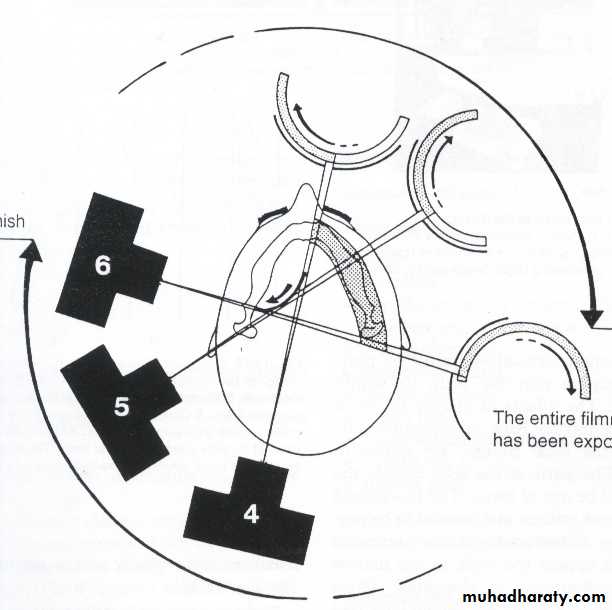

Focal trough layer the area between the x ray source and the image receptor that will be imaged distinctly on the panoramic radiograph.

This position is often referred to as the patient being positioned with the ala tragus line in a minus 50 position. At the same time this position allows the ala tragus line to be correctly positioned. The panelipse panorex i and panorex ii use the ala tragus line for patient positioning. Notice the panoramic image is divided into 9 areas that make up the 6 zones that you must learn to picture each panoramic radiograph or image in your mind s eye.

The angle between this line and the horizontal plane is 3on the panorex and 4on the. Focal trough layer that area between the x ray source and the image receptor that will be imaged distinctly on the panoramic. In other words the ala of the nose should be slightly inferior to the height of the tragus. These zones are as follows.